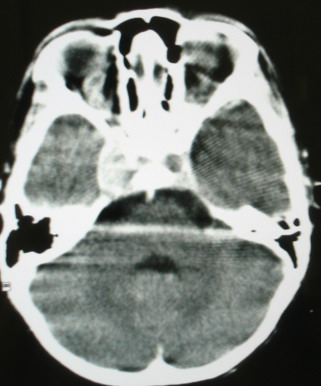

m/8y/,右侧眼睑下垂数日,发育良好,无外伤史,无头痛、恶心、呕吐,学习成绩良好。

ct意见:1、颅内血管畸形。2、右侧海绵窦血管瘤(颈内动脉海绵窦段动脉瘤)。3、脑萎缩。4、建议mr或dsa.

平扫片(骨窗未见异常)